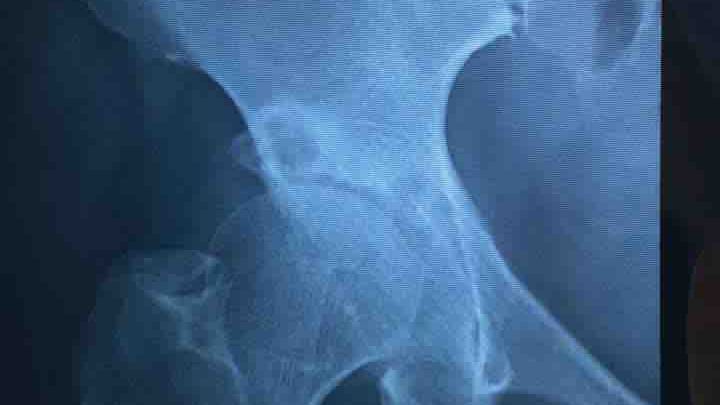

To all my family, friends, friend of friends, colleagues and everyone that can help, this is my friend Gloria. We have known each other for about 10 years now and she resides in El Salvador. She is struggling with medical care expenses, due to COVID-19 restrictions causing her business to shutdown for several months. She moved into our house in Santa Tecla, because she could not continue to pay her own house until she got back on her feet, but now she is faced with another hip surgery, due to a fall earlier in the year when she broke her other hip. Gloria is a very proud person and it took a lot of begging her to allow me to do this for her, because has always been the provider in her family. She is seeing her long time customers and trying to retain her cliental even when she is on crutches and in extreme pain. Her hip surgery, physical therapy and medication costs is going to run over $10k.